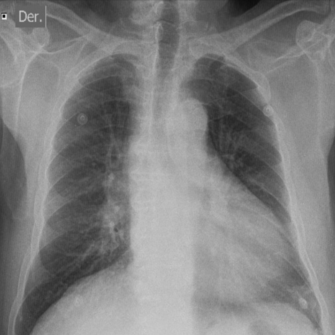

Se procedió, entonces, a realizar un electrocardiograma (ECG) (figura 1) que evidenciaba ritmo sinusal, bloqueo auriculoventricular (AV) de primer grado y bloqueo completo de rama izquierda. La radiografía de tórax (figura 2) mostraba un índice cardiotorácico aumentado, sin otras alteraciones a destacar. La analítica de laboratorio fue normal. Concomitantemente se solicitó una tomografía de cráneo que evidenciaba a nivel parietal derecho una imagen lineal hiperdensa en relación con hemorragia subaracnoidea (HSA) traumática.

Figura 2: Radiografía de tórax enfoque de frente. Se evidencia aumento del índice cardiotorácico sin otras alteraciones patológicas.